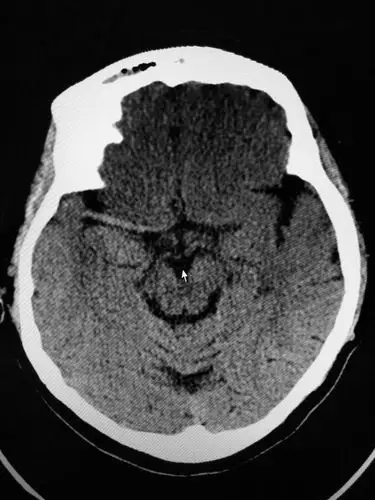

右侧大面积脑梗死,可见右大脑中动脉高密度征,提示血栓形成